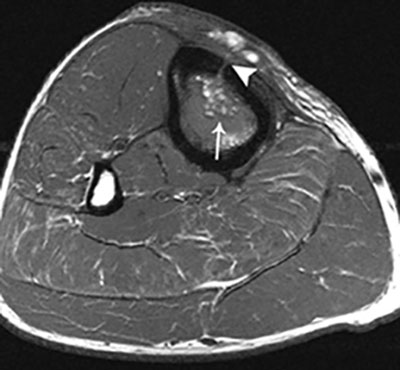

Figure 9

Fat globule sign on T1–WI. Axial T1–WI showing fat globules (white arrow) within the bone marrow edema of the tibia. In addition, there is a cortical defect – also known as the cloaca – perforating the ventromedial cortex of the tibia (white arrowhead).